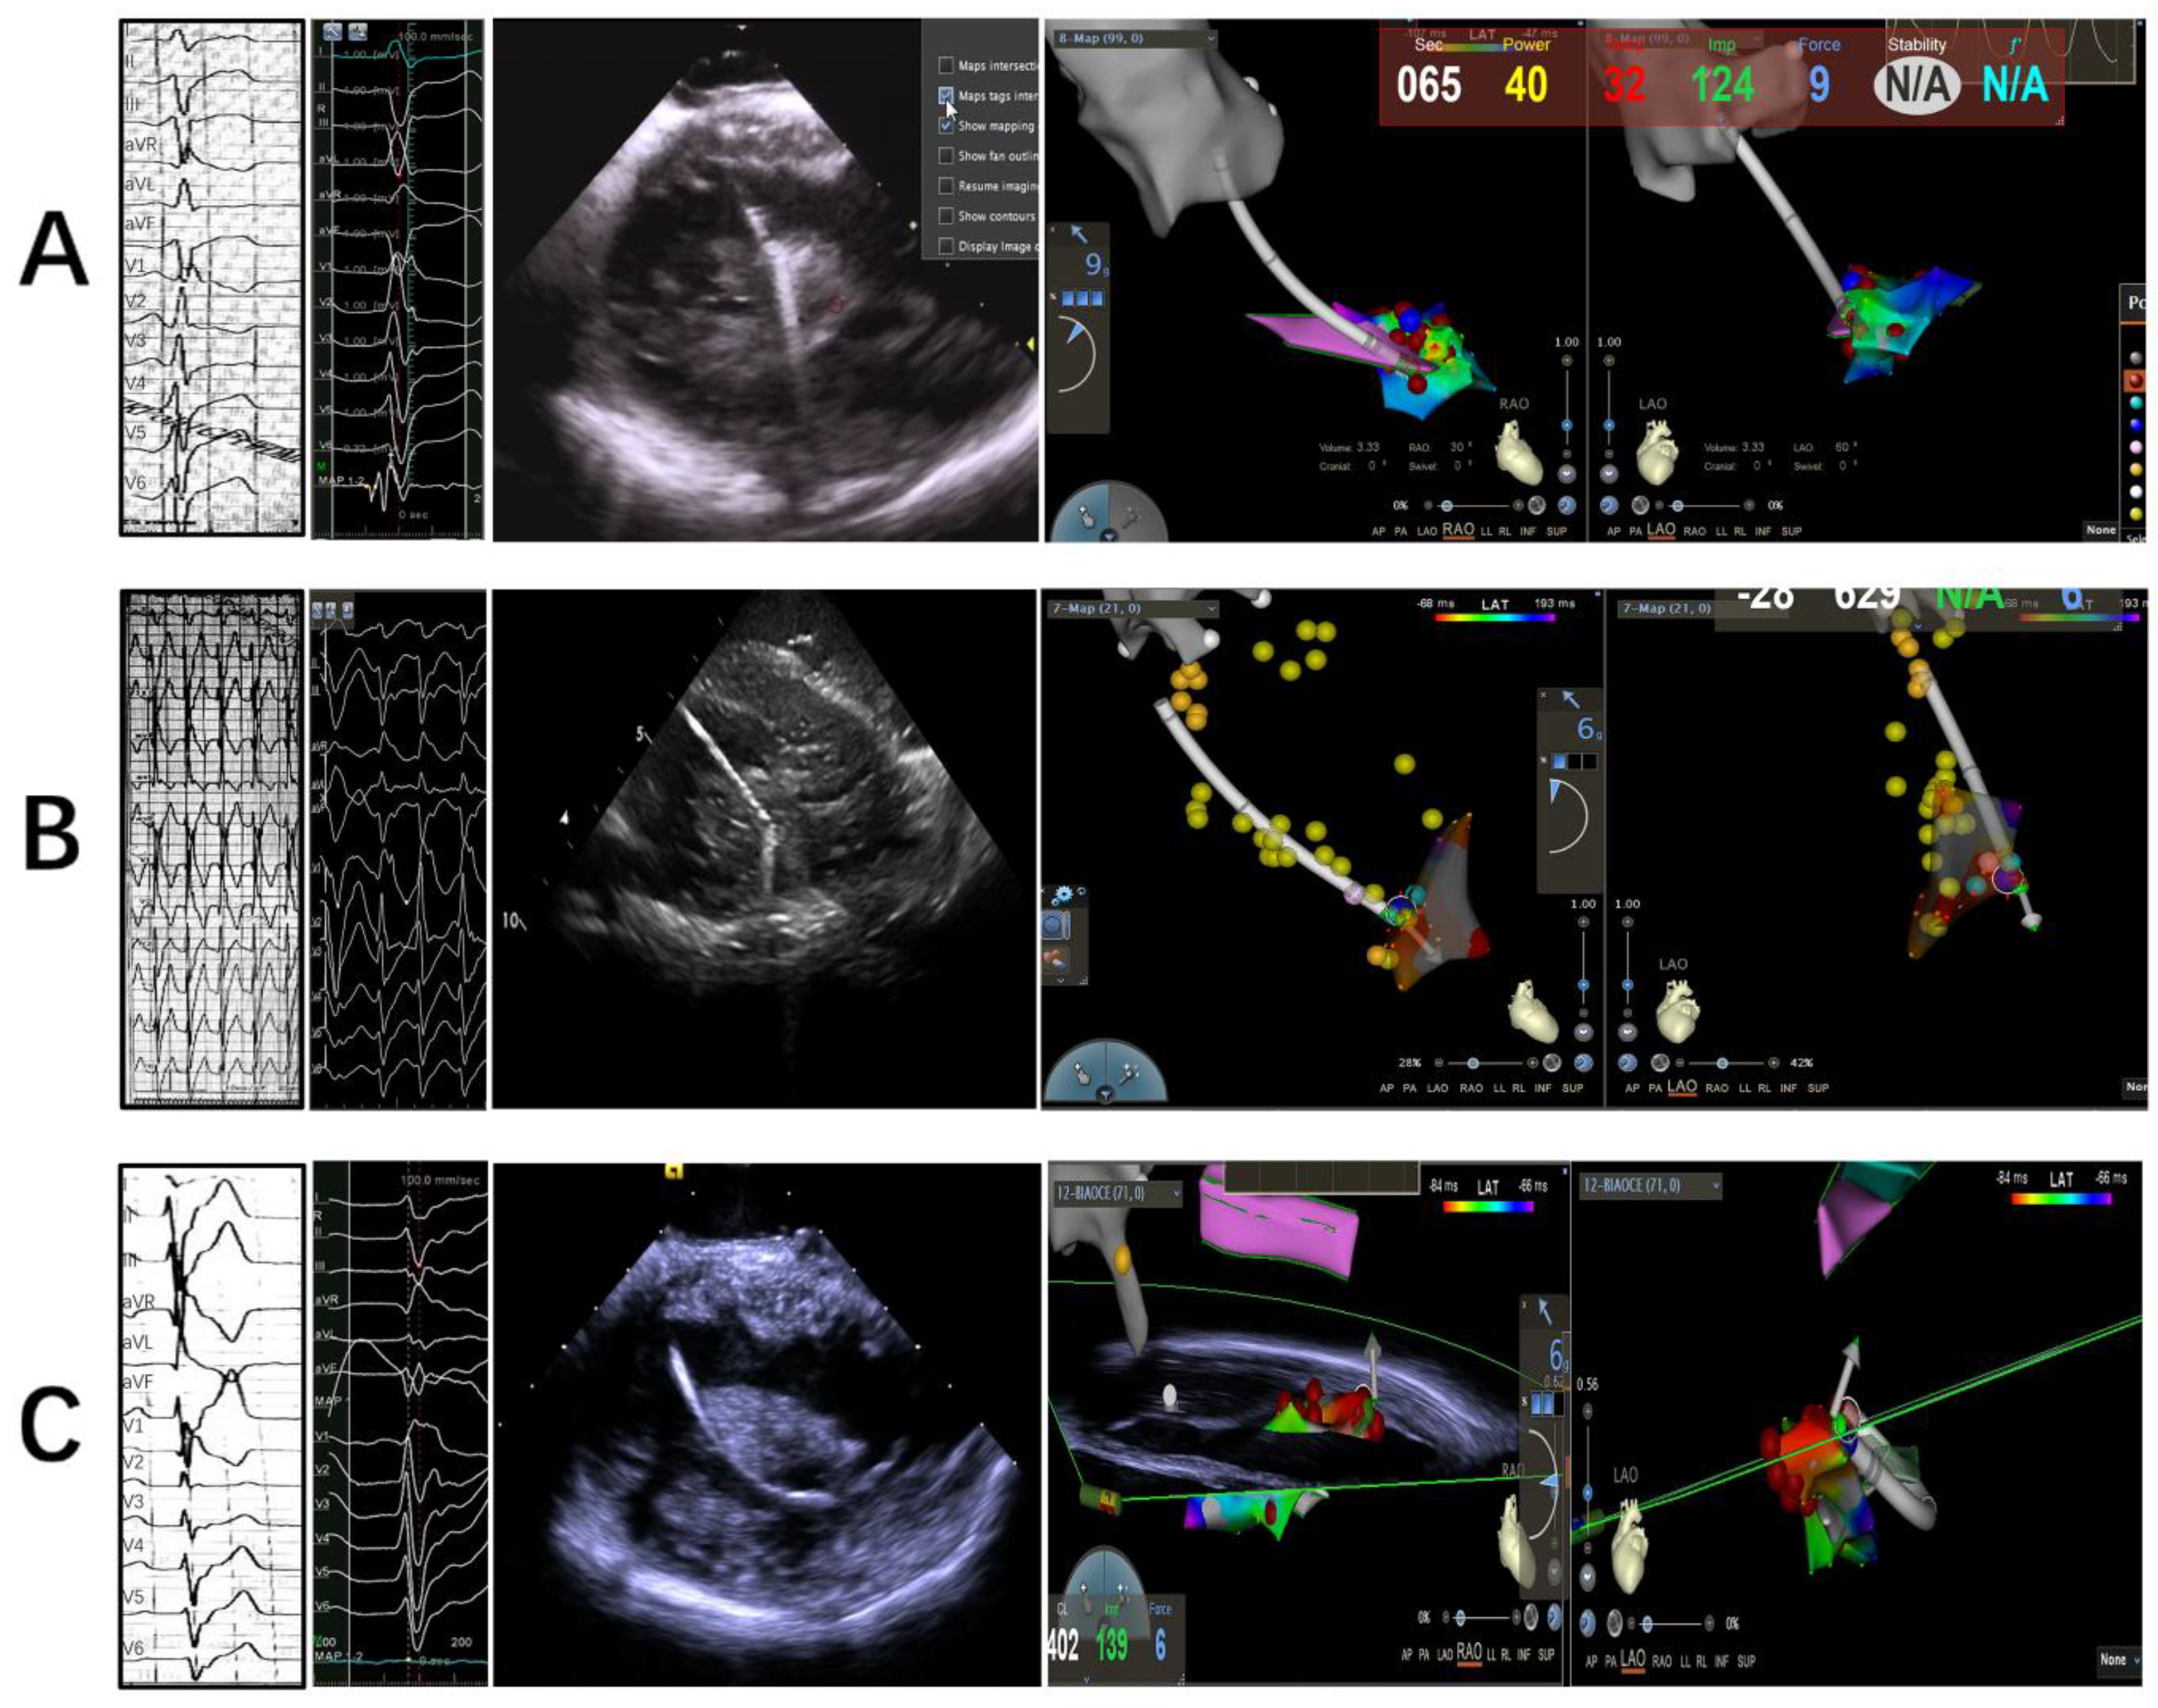

2.2. Electrophysiology Study, Mapping and Ablation

2.2.1. Intracardiac Echocardiography

2.2.2. Mapping and Ablation